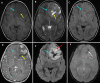

Neuroblastoma represents the most common solid extracranial tumor in children under 5, accounting for 8% to 10% of all childhood cancers. Primary central nervous system (CNS) neuroblastomas are a very rare location and only few cases are available in the literature. It was first described in 1973 by Hart and Earl as supratentorial primitive neuroectodermal tumors. Clinical presentation is highly variable and depends on the initial location of the tumor. Regarding imaging, primary brain neuroblastoma shows no pathognomonic appearance on brain computed tomography (CT) whether or not enhanced or magnetic resonance imaging (MRI). There were no standard guidelines available for the adjuvant treatment in case of primary CNS neuroblastoma. Surgery remains the main and the first tool toward these lesions. Radiotherapy associated or not to chemotherapy is offered based on patient´s age. Here, the authors report a new pediatric case of primitive central nervous system neuroblastoma revealed by an intracranial hypertension syndrome and confirmed by both histopathological and immunohistochemistry study after a gross total surgical excision. The postoperative course was uneventful and the child had good recovery.